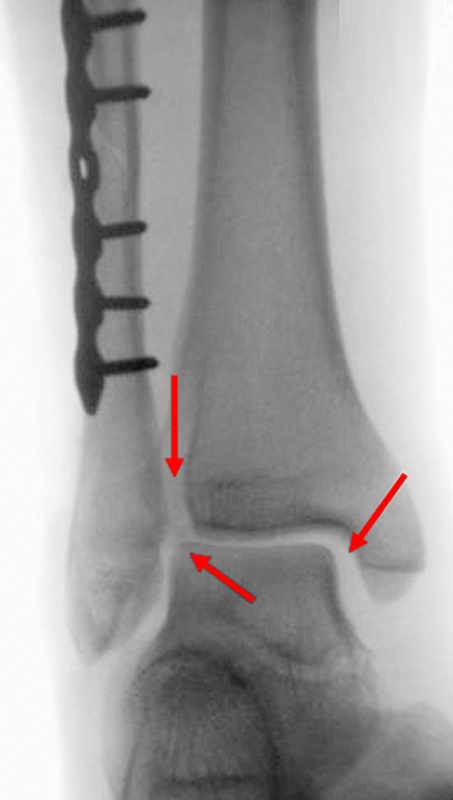

Seit einer Untersuchung von Nelson und Jensen aus dem Jahre 1940 wird allgemein akzeptiert, dass die Indikation zur Osteosynthese des Tibiahinterkantenfragments nur dann besteht, wenn die Größe mehr als ein Drittel (nach zahlreichen Autoren auch ein Viertel) der Gelenkfläche beträgt (Abbildung 15) 25. Dieses bis heute allgemeinakzeptierte Vorgehen basiert auf der Beobachtung von lediglich acht unterschiedlich versorgten Patienten. Seither gibt es keine weiteren klinischen Studien, die dieses Vorgehen stützen. Mittlerweile gibt es allerdings zunehmend Hinweise, dass bei der Versorgung des posterioren Malleolus viele andere Faktoren eine wichtige Rolle spielen 26. Da an der Tibiahinterkante das Lig. tibiofibulare posterius ansetzt (Abbildung 16), wird durch die offene Reposition und Stabilisierung die Integrität und die physiologische Spannung der hinteren Syndesmose rekonstruiert (Abbildung 17). Dies ist entscheidend für die anatomische Reposition der Fibula in der Tibiainzisur.

Gardner et al. konnten beispielsweise zeigen, dass die offene anatomische Reposition der Tibiahinterkante der Stabilisierung mittels Stellschraube überlegen war und gleichzeitig mit einer geringeren Rate an postoperativen Fehlstellungen der Fibula in der CT-Kontrolle einherging 2728. Aus Sicht der Autoren ist prinzipiell die Stabilisierung über eine direkte Reposition indiziert, wenn die Größe des Fragmentes dies erlaubt. Bei gleichzeitigem Vorliegen einer Fraktur des lateralen und/oder medialen Malleolus sollte zunächst die Versorgung der des Tibiahinterkantenfragments erfolgen. Dies erlaubt die radiologische Kontrolle der Reposition und Osteosynthese-Lage, welche durch eine zuvor aufgebrachte Fibula-Platte häufig erschwert ist 29. Dafür werden die Patienten in Seitenlage gelagert. Dies erlaubt die direkte Versorgung der posterioren Malleolusfraktur über einen posterolateralen Zugang 30. Das sehr kräftige Periost wird im Frakturverlauf inzidiert und aus den Frakturspalt entfernt, so kann eine anatomische Reposition erfolgen. Entsprechend der Fragmentgröße erfolgt entweder die Versorgung mittels Drittelrohrplatte in Antiglide-Technik oder eine Zugschraubenosteosynthese. Die Versorgung der Fibula-Fraktur gelingt über den gleichen Zugang. Zur Versorgung des medialen Malleolus wird der Patient auf den Rücken umgelagert. Dies kann bei entsprechender Vorbereitung ohne erneutes steriles Abdecken erfolgen. Durch dieses Vorgehen konnte im eigenen Kollektiv die Notwendigkeit einer Stabilisierung der Syndesmose mit Stellschraube/Tight Rope deutlich reduziert werden.